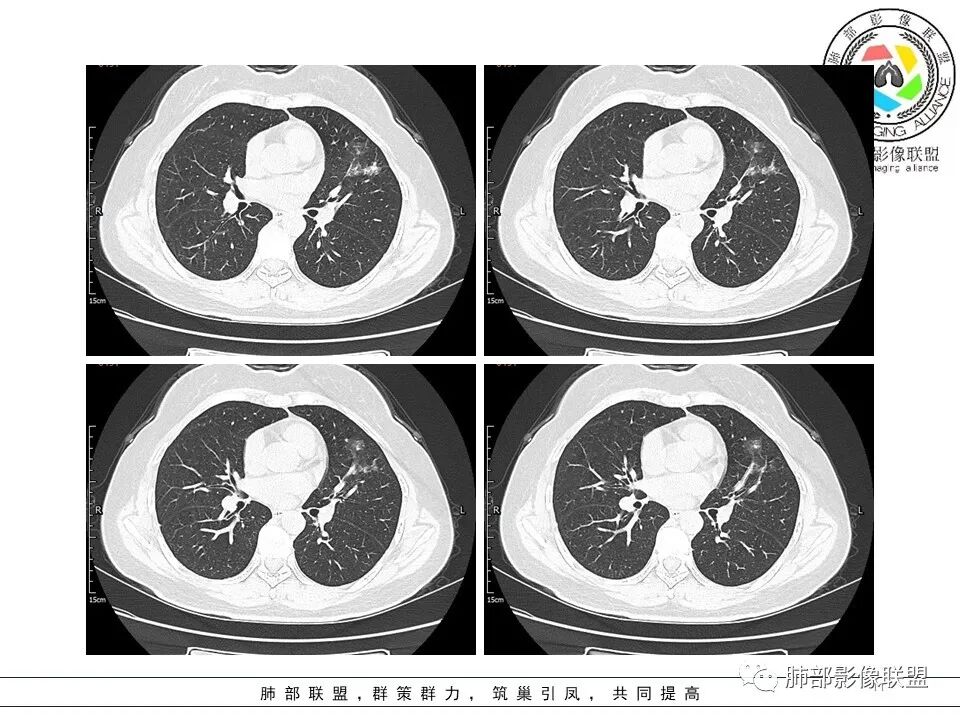

左肺上叶ggo,短毛刺,空泡征,6个月后复查病灶似变大,有轻度不均质强化,腺癌?胸膜下粟粒结节,无变化,良性?

分叶结节,内部结构杂乱,边缘板刷样毛刺,GGO边界清楚

胸膜牵拉

月牙铲?

常规要考虑腺癌

左肺上叶胸膜下不规则结节影,分叶、粗短毛刺,胸膜牵拉等,像个“刺头”。

未见钙化,也未显示液化坏死或空洞。

与支气管相关,但取层未能显示支气管进入情况。

1.病灶周围向几个方向膨出的边界清楚的磨玻璃影,这些磨玻璃影时隔几个月依然,几乎可以排除出血及一般的炎性改变。

2.病灶的胸膜牵拉线与其间病灶胸膜侧的磨玻璃边构成朝向胸壁的“月牙铲”结构,这种影像学表现某种程度上反映出病理学特征——病灶收缩+小叶间隔阻挡。

3.病灶实性密度区强化明显,这有助于我们区分一些其他类似病灶,如结核灶等!

4.邻近未见树芽征及卫星灶等。

结合临床,应当高度怀疑浸润性肺腺癌!